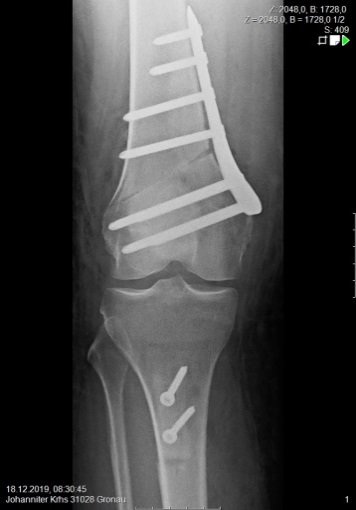

Bony correction: axis and tuberosity

In surgical therapy, the pathology must be eliminated in order to ensure the stable running of the patella in the future. There are a variety of options available for this, which must be used in a targeted manner. These include suturing of the MPFL (medial patellofemoral ligament), plastic surgery of the MPFL, axis corrections, reshaping of the gliding groove (trochleoplasty), and modification of the patellar tendon insertion (offset of the tibial tuberosity).